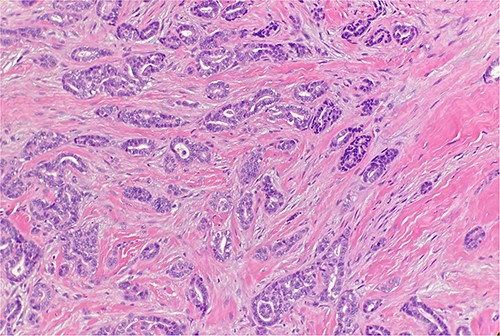

Received are multiple fragments of pink tan soft tissue. Microscopic examination reveals infiltrative growth pattern, presence of atypia and lack of myoepithelial cells (Fig. 1). This supports the diagnosis of a well-differentiated sclerosing ductal adenocarcinoma. Patient does not have a history of a prior adenocarcinoma elsewhere; the findings are consistent with a primary cutaneous adenocarcinoma of sweat/duct origin.

Microscopic examination reveals infiltrative malignant glands with angulated contours. H&E ×20.